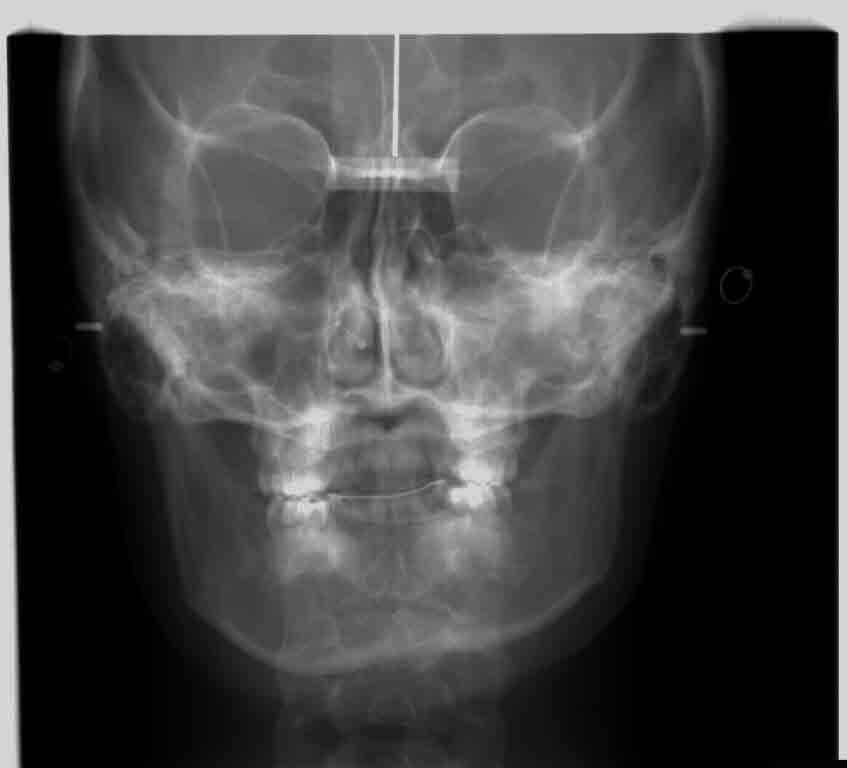

my crooked jaw pre/post Is My Jaw Crooked But if it’s not obvious, how do you know if your jaw is crooked? Learn about jaw misalignment, including causes, related health problems, and. A crooked jaw, also known as mandibular misalignment, is a condition that can significantly impact both your oral health and. Your jaw plays a crucial role in your oral health and affects your ability to eat,. Is My Jaw Crooked.

my crooked jaw i got issues, ya'll Is My Jaw Crooked But if it’s not obvious, how do you know if your jaw is crooked? Trauma, tmj, teeth misalignment, and more can lead to an uneven jaw. Get rid of asymmetrical jaw & chin naturally. A crooked jaw, also known as mandibular misalignment, is a condition that can significantly impact both your oral health and. In this blog, we’ll discuss the. Is My Jaw Crooked.

my crooked jaw pre/post Is My Jaw Crooked To determine whether you have a crocked jaw, here are some symptoms you should pay attention to: But if it’s not obvious, how do you know if your jaw is crooked? Learn about jaw misalignment, including causes, related health problems, and. Misaligned jaws can result from genetics, childhood habits, injuries, and other factors. Trauma, tmj, teeth misalignment, and more can. Is My Jaw Crooked.